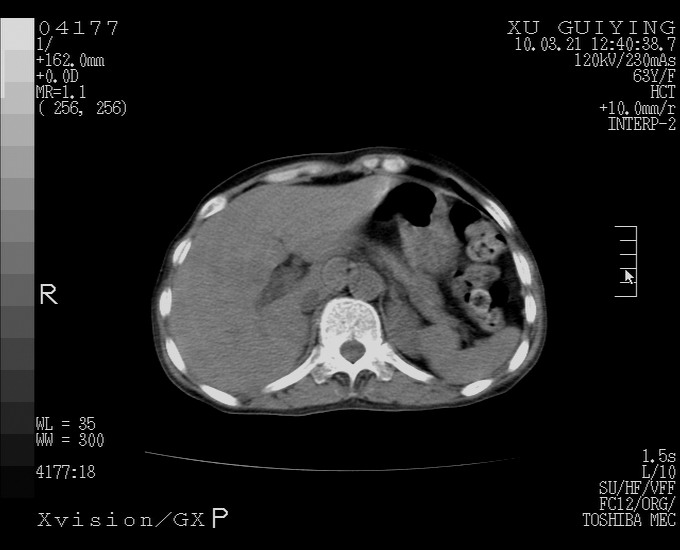

怎么没有增强呢?胆囊那么大,密度有些高啊。

慢性胆囊炎,胆囊占位不排除,建议增强或彩超。

考虑胆囊炎 不除外泥沙样结石

胆囊体积增大,胃窦壁增厚

胆囊体积增大

胆囊体积增大,密度不均匀,结石不除外;胃壁增厚,考虑胃癌,建议增强。

胆囊体积增大 ,建议超声检查。

胆囊体积增大,密度增高,较均匀,外缘也较光滑,应考虑胆囊炎。因为胃未充盈,不好说壁增厚。肝左叶及脾门处见低密度灶,有可能是血管瘤,不排除囊肿。建议超声检查或强化。

胆囊增大,原因待查。